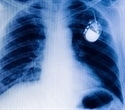

The device, recently approved by the Food and Drug Administration, is called the Medtronic CoreValve® System. On March 28, Loyola became the first Illinois hospital to implant the device in a patient who was not part of a clinical trial. Prior to the FDA approval, the device was available only to patients enrolled in a clinical trial.

The new device is deployed with a catheter, which is inserted in an artery in the groin and guided up to the heart. Once in place, the artificial valve takes over the function of a diseased valve. The system is much less invasive than traditional open-heart surgery.